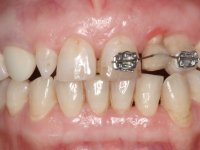

• Orthodontic treatment to close diastema between maxillary central incisor teeth and slow tooth traction 2.2.

Treatment began with re-preparation of the cast post and core, with the purpose of placing the cervical finishing lines with an intra-sulcular location and simultaneously making a suitable temporary crown. With a very simple orthodontic treatment, the diastema was closed between the upper central incisors, and this position was stabilized with a wire placed on the palatal surface of the central, functioning as containment. Later, a slow orthodontic traction of tooth 2.2 was attempted, in order to reduce, although very slightly, the vertical bone loss in this area. At the end of the traction, tooth 2.2 was extracted and the area was provisionally rehabilitated with a composite resin crown bonded to the adjacent teeth. A dental implant was placed in the area of tooth 2.2 and the temporary crown was again bonded to resin, provisionally rehabilitating the patient during osseointegration. In tooth 1.3 a gingivectomy with an electric scalpel was performed, with the intention of raising the cervical level of 1.3 achieving greater harmony with tooth 2.3. Stabilized soft tissues were impressed using the open tray technique with putty and light addition silicones. Collection of the color of both the dental component and soft tissues was done by the ceramist in the office. In the laboratory, the impressions were transferred to plaster and gave origin to work models that were properly analyzed. It was decided to assemble a metal-ceramic abutment screwed onto the implant. This abutment was cast with a noble alloy and subsequently coated with coronary and gingival ceramics. Due to the inclination of the implant, the screwing inevitably conditioned the exit of the screw hole through the vestibular surface. In order to conceal this situation, the design of the abutment has already been conceived with the intention of accommodating on the vestibular surface the bonding of a feldspathic veneer. This abutment was tested in the mouth and adjustments were made in the gingival ceramic component. Its adaptation to the soft tissues was done in a subtractive way, with a drill, as well as additive, adding resin composed of gingival tonality.

This addition of resin would guide the ceramist in the final placement of the gingival tonality ceramic. The crown that would rehabilitate tooth 1.3 was cemented in this test session with glass ionomer cement, reinforced with composite resin. Once the laboratory work was finished on the veneer for tooth 1.2, the abutment, and the veneer for the implant, this was bonded in the mouth, after placement of the absolute insulation. The work completely satisfied the patient. For eight years, the patient had periodical check-ups, and was pleased with the treatment, but also began to show interest in an aesthetical intervention on the upper central incisors. Once the second phase of our intervention was decided, dental preparation of teeth 1.1 and 2.1 was performed for the placement of two feldspathic veneers. Particular care was taken in the distal inter-proximal preparation adjacent to the abutment of the implant.

The axis of insertion of the veneer in relation to the abutment was very carefully evaluated. The feldspathic veneers were prepared in the laboratory and then bonded to the mouth after placing absolute insulation. One year later, we began our third phase of treatment, after the veneer in tooth 2.1 fractured. A dental preparation was done on the bonded veneer, seeking to extend the distal inter-proximal interface more to the palate. The objective would be to move the veneer to a more palatine contact point. Preparation of tooth 1.2 was limited to creating an insertion axis. After preparation, the total crown and laboratory veneer were bonded to the mouth. First, the crown was bonded using a relative insulation with Teflon, later the veneer was bonded after the absolute insulation placement. In the crown, I used this type of insulation to avoid the use of staples. It would be difficult to apply due to the shape and size of the tooth, and would also be aggressive to the soft tissues. After bonding procedures, the occlusal integration of the work was evaluated.